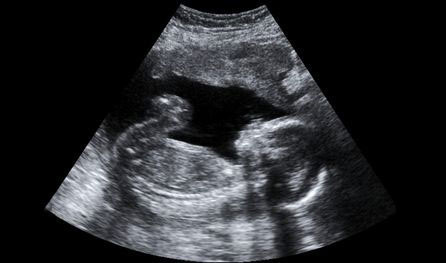

A Pfeiffer-szindróma már a csecsemő világra jötténél jelen van, hiszen egy születési rendellenesség, amit a tévhitek ellenére nem lehet, vagy csak nagyon nehéz felismerni. Az anyaméhben töltött hónapok alatt elvégzett vizsgálatok az esetek túlnyomó többségében nem mutatnak ki eltérést az egészséges babák értékeivel szemben, csupán a kissé nagyobb méretű koponya az, ami első jelként szembetűnő lehet. Általában csak a születés után ismerik fel ezt a súlyos testi rendellenességet, ami gyermekkorban a szemek behunyásának lehetetlenségével és a beszédképesség, valamint a járás elmaradottságával jár.